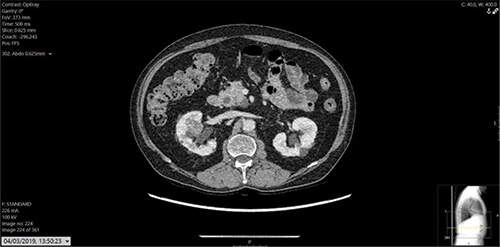

Figure 2: 2.7cm abnormal, heterogeneous mass seen anteriorly in the upper pole of right kidney, highly suspicious of RCC. This was not seen previously.

Blood work reported estimated glomerular filtration rate (eGFR) of 26, creatinine 161, and normal liver functions tests (LFTs). The CT at initial presentation with renal cancer and the recent contrast CT chest, abdomen and pelvis are shown in Figures 1-3. MRI of the skull reported a 3.3x2.3cm soft tissue heterogeneous lesion involving the parietal bone and invading the dura (Figure 4). Ultrasound-guided scalp biopsy showed infiltration of fibrous tissue by sheets of epithelioid tumour cells with abundant clear cytoplasm and intervening prominent blood vessels. The tumour cells expressed RCC, CD10 and PAX 8. They did not express CK7, CK20, TTF-1, Gata3 and WT-1. The conclusion was metastatic RCC.